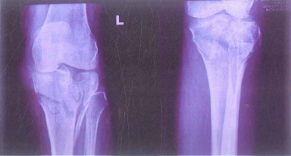

Thông thường X-quang khớp gối thẳng, nghiêng đủ để chẩn đoán. Những trường hợp khó cần chụp thêm X- quang nghiêng 40 độ, nghiêng trong nhìn rõ mâm chày ngoài và xoay ngoài nhìn rõ mâm chày trong.

Hình 11.4. X-quang gãy mâm chày